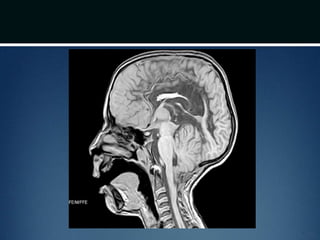

Diagnosis

โ€ข MRI โ€“ Craniovertebral junction and entire

spinal cord

โ€ข 50-75% patients have syringomyeliasyrinx

โ€ข CT โ€“ bony abnormality; plain films for

evaluating stability issues

โ€ข Dynamic MRI (cine MRI) โ€“ for CSF flow

Diagnosis โ€ข MRI โ€“Craniovertebral junction and entire spinal cord โ€ข 50-75% patients have syringomyeliasyrinx โ€ข CT โ€“ bony abnormality; plain films for evaluating stability issues โ€ข Dynamic MRI (cine MRI) โ€“ for CSF flow around the CVJ